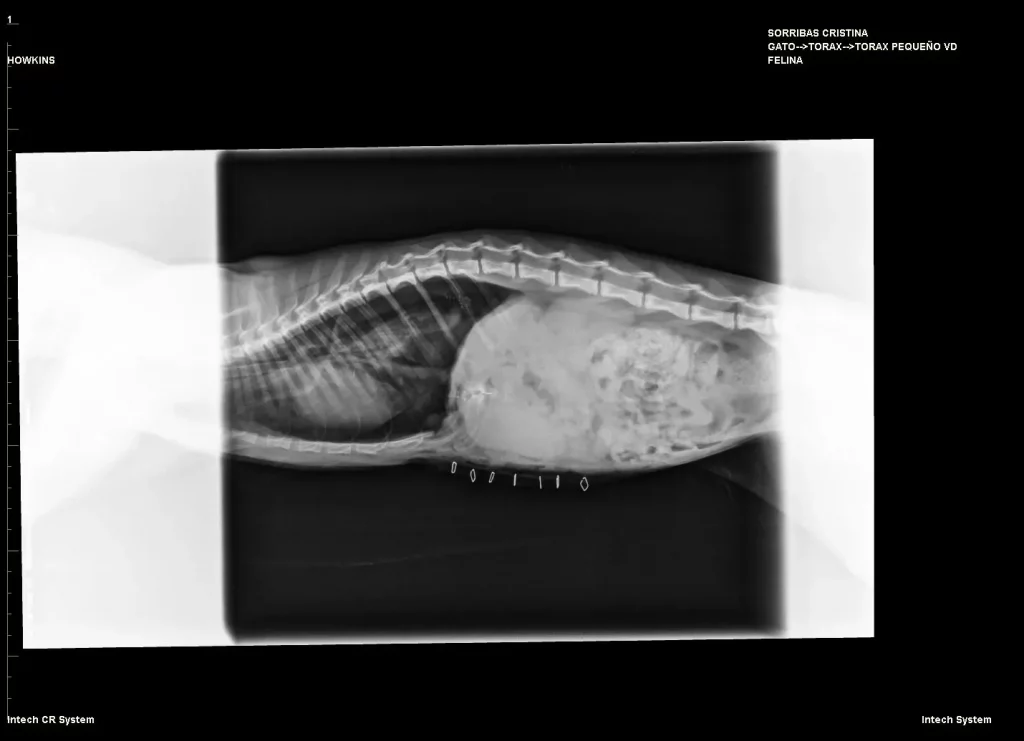

Mismo paciente después de la cirugía correctiva. Órganos recolocados a ala cavidad abdominal.

• Radiografía de tórax y abdomen: permite ver los órganos desplazados y el contorno del diafragma.